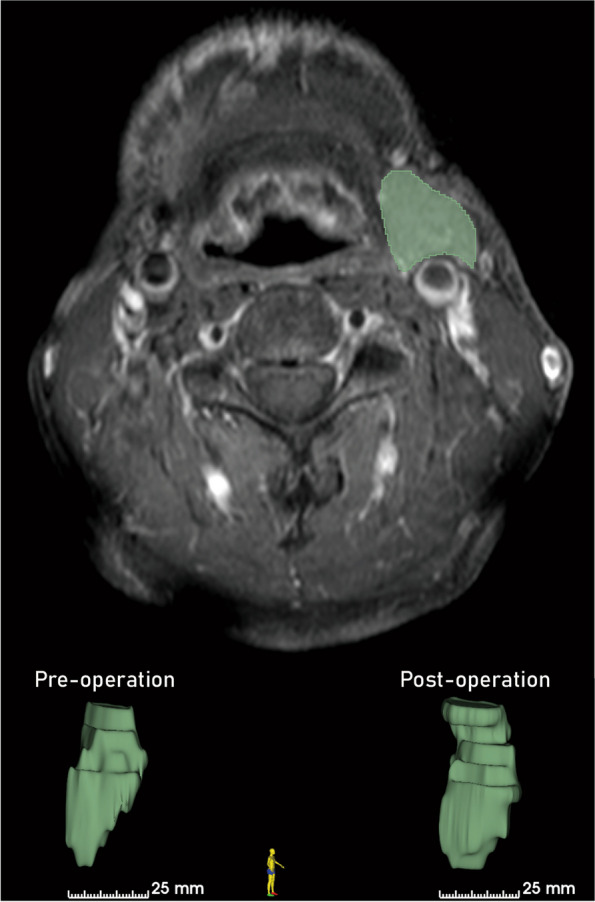

Method: This retrospective study involved patients with oral cancer who underwent unilateral submandibular gland excision and ipsilateral neck dissection at Gangneung-Wonju National University Dental Hospital between 2008 and 2023. Patients were included if they had preoperative and follow-up 3D radiological images. The contralateral submandibular gland volume was measured using 3D Slicer software on preoperative, post-operative, and follow-up radiographic data.

Results: The mean volume change of the contralateral submandibular gland was 1.35 ± 2.06 cm3, with a mean change ratio of 1.18 ± 0.24. These changes were statistically significant (p = 0.006). Other factors such as age, gender, and radiotherapy did not significantly affect the volume change ratio (p > 0.05).